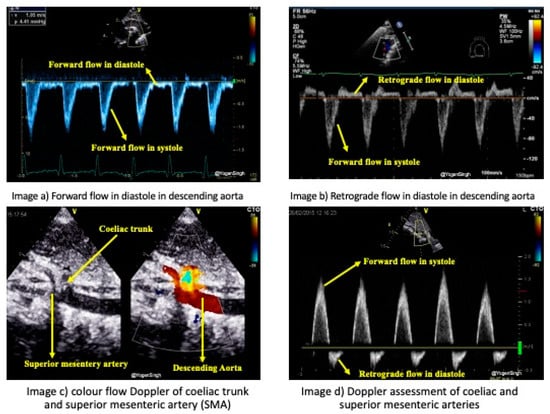

3.3. Echocardiographic Assessment of Systemic Hypoperfusion

Systemic hypoperfusion occurs in the presence of an hsPDA when blood diverts away from the systemic circulation below the ductus arteriosus level. Doppler evaluation can be used to assess the degree of systemic steal in which retrograde or absent blood flow is seen during the diastole in the post-ductal descending aorta, coeliac trunk, superior mesenteric artery, or renal artery [11,17,21,23,26,27]. Doppler flow patterns can be acquired in the descending aorta from the suprasternal view by distally positioning the pulsed wave Doppler sample gate to the ductal ampulla (Figure 6a,b). A Doppler assessment of the coeliac trunk or superior mesenteric artery is obtained from the subcostal longitudinal view—a pulsed wave Doppler sample gate is placed in the coeliac or superior mesenteric artery after optimizing the image so that the angle of insonation is minimal, <10–15 degrees is recommended. (Figure 6c,d) [17,26]. A Doppler assessment of the anterior or middle cerebral artery can be used to evaluate the hsPDA’s effect on brain perfusion, and a similar flow pattern is seen—absent or retrograde flow during diastole is observed in the presence of an hsPDA.

Figure 6. Doppler assessment of blood flow in the descending aorta post-ductally, in the coeliac trunk, and the superior mesenteric artery. (a) shows forward blood flow during systole and diastole in the descending aorta from the suprasternal arch view. (b) shows retrograde blood flow during diastole in the descending aorta, indicating ‘ductal steal’ in the presence of an hsPDA. (c) shows the coeliac and superior mesenteric arteries from the subcostal longitudinal color compare view, and (d) shows retrograde blood flow during diastole in the coeliac and superior mesenteric arteries, indicating ‘ductal steal’ similar to flow in the descending aorta.